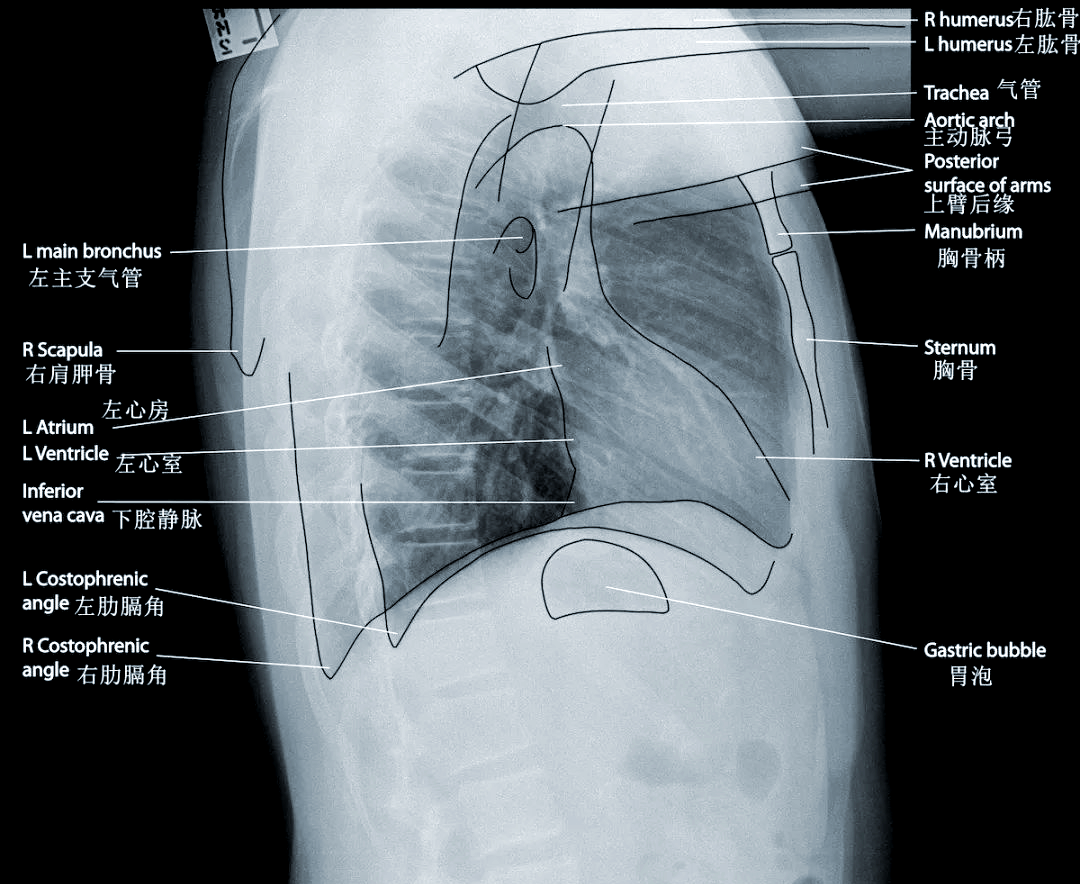

X线适用于胸部骨骼等部位的初步检查CT适用于胸部肝脏胰腺等部位的详细检查,对肿瘤具有较高的分辨率B超适用于胆道肝脏脾脏等腹部器官的检查,以及部分妇科和儿科疾病的检查MRI适用于颅脑脊柱脊髓关节等软组织的检查,对病变组织的敏感度较高以下是相关图片展示在选择影像;X线和CT的主要区别如下成像原理X线X线平片是所有的人体组织重叠在一起形成的影像CTCT是断层成像,即把不同组织之间像切片一样,一张一张地分别显示出来影像清晰度X线由于组织重叠,影像可能不够清晰,有时会有组织互相遮挡的情况CT断层成像能够显示更多的解剖细节,组织之间很少会有;X线与CT的主要区别如下成像原理X线X线是一种波长范围在001到10纳米之间的电磁辐射形式当X线穿透人体时,由于人体各组织对X线的吸收程度不同,最终在X线胶片上形成不同的灰度图像CTCT是通过X线对人体某一部位进行逐层扫描,然后由计算机将扫描得到的多个层面的信息进行处理,重建出该部位的;X线片优点是成像速度快价格便宜缺点是只能呈现黑白二维图像,且存在辐射CT优点是成像细节丰富可以三维成像缺点是辐射量大尽管CT的辐射量高于X线片,但在医疗诊断中仍然是安全的,医生会根据患者的具体情况来决定是否需要进行CT检查MRI优点是没有辐射成像细节丰富可以三维成像缺点是。